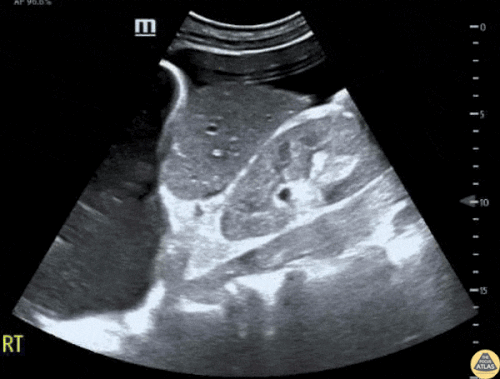

Ekokardiyografi (EKO): Anormal Patolojik Aort Örnekleri

Diseksiyon Flebi ile Sakküler Abdominal Aort Anevrizması

Abdominal Aort Anevrizmasının Sagittal Görünümü

Öksürük ile Başvuran Abdominal Aort Anevrizması

İntramural Trombüs İçeren Abdominal Aort Anevrizması

Normal aort çapı 3 cm’den küçüktür. Herhangi bir seviyede çapın 5 cm’den büyük olması, uygun klinik bağlamda akut rüptür olasılığını akla getirmelidir.

Aort en az 4 seviyede görüntülenmelidir ve özellikle infrarenal segment dikkatle değerlendirilmelidir; çünkü AAA en sık bu bölgede görülür. İdeal olarak aortun tamamı kesintisiz şekilde taranmalıdır; ancak bu her zaman mümkün olmayabilir.

Dış duvardan dış duvara ölçüm yapılmasının nedeni, anevrizma ve diseksiyonun damar duvarı içinde yer alabilmesidir. Bu nedenle ölçüm her iki duvarı da içermelidir.